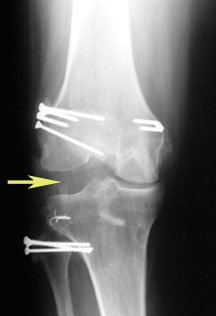

As you will learn, deficiency of the PLC causes an abnormal increase in the amount of joint space between the femur and tibia on the lateral (outer) part of the knee. This is termed abnormal lateral joint opening – and this places harmful forces on a healing ACL or PCL graft that eventually causes the graft to fail.

This is clearly evident in the x-ray on the left as shown by the yellow arrow – compared to the normal, uninjured knee on the right. [The white things are the metal fixations put in during the operation.]